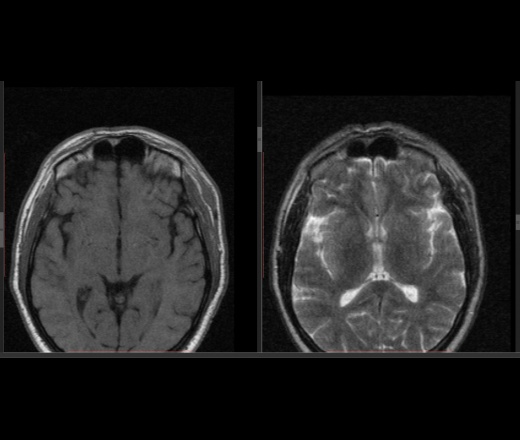

дифференциальная диагностика ganglion ,нодулярный фасциит,нейрофиброма,дерматофиброма